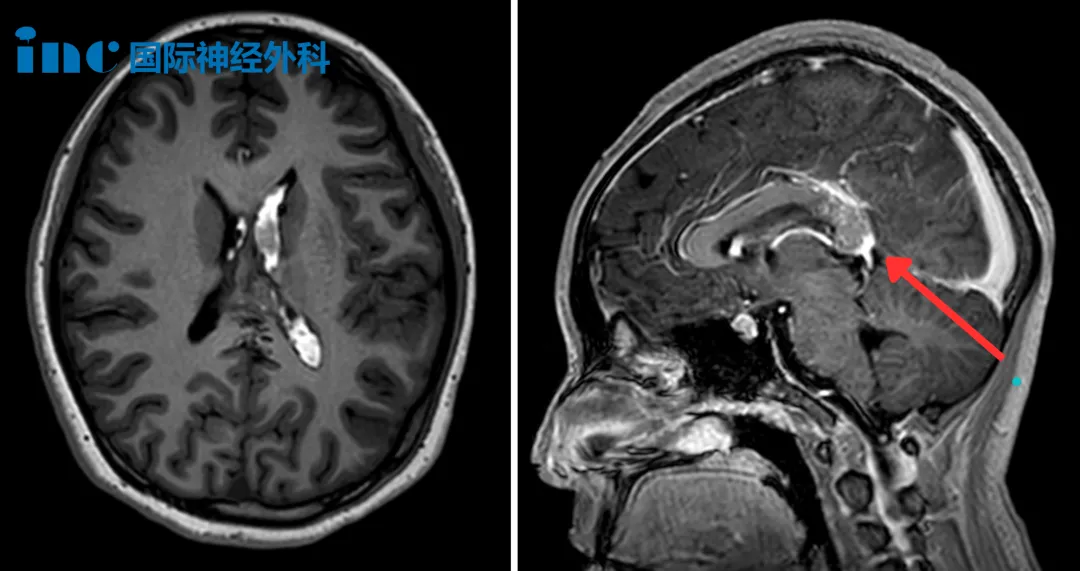

“小小英雄”打敗近6cm巨大顱咽管瘤!家人的愛支撐著他戰(zhàn)無不勝

他是家里所有人的希望,如果他出了問題,我們很難重新開始。伴隨著田先生(小安爸爸)的講述,我們看到了一個愛意滿滿的家庭縮影。當(dāng)午后的陽光照進(jìn)這一間小小的病房時,6歲的小安正...